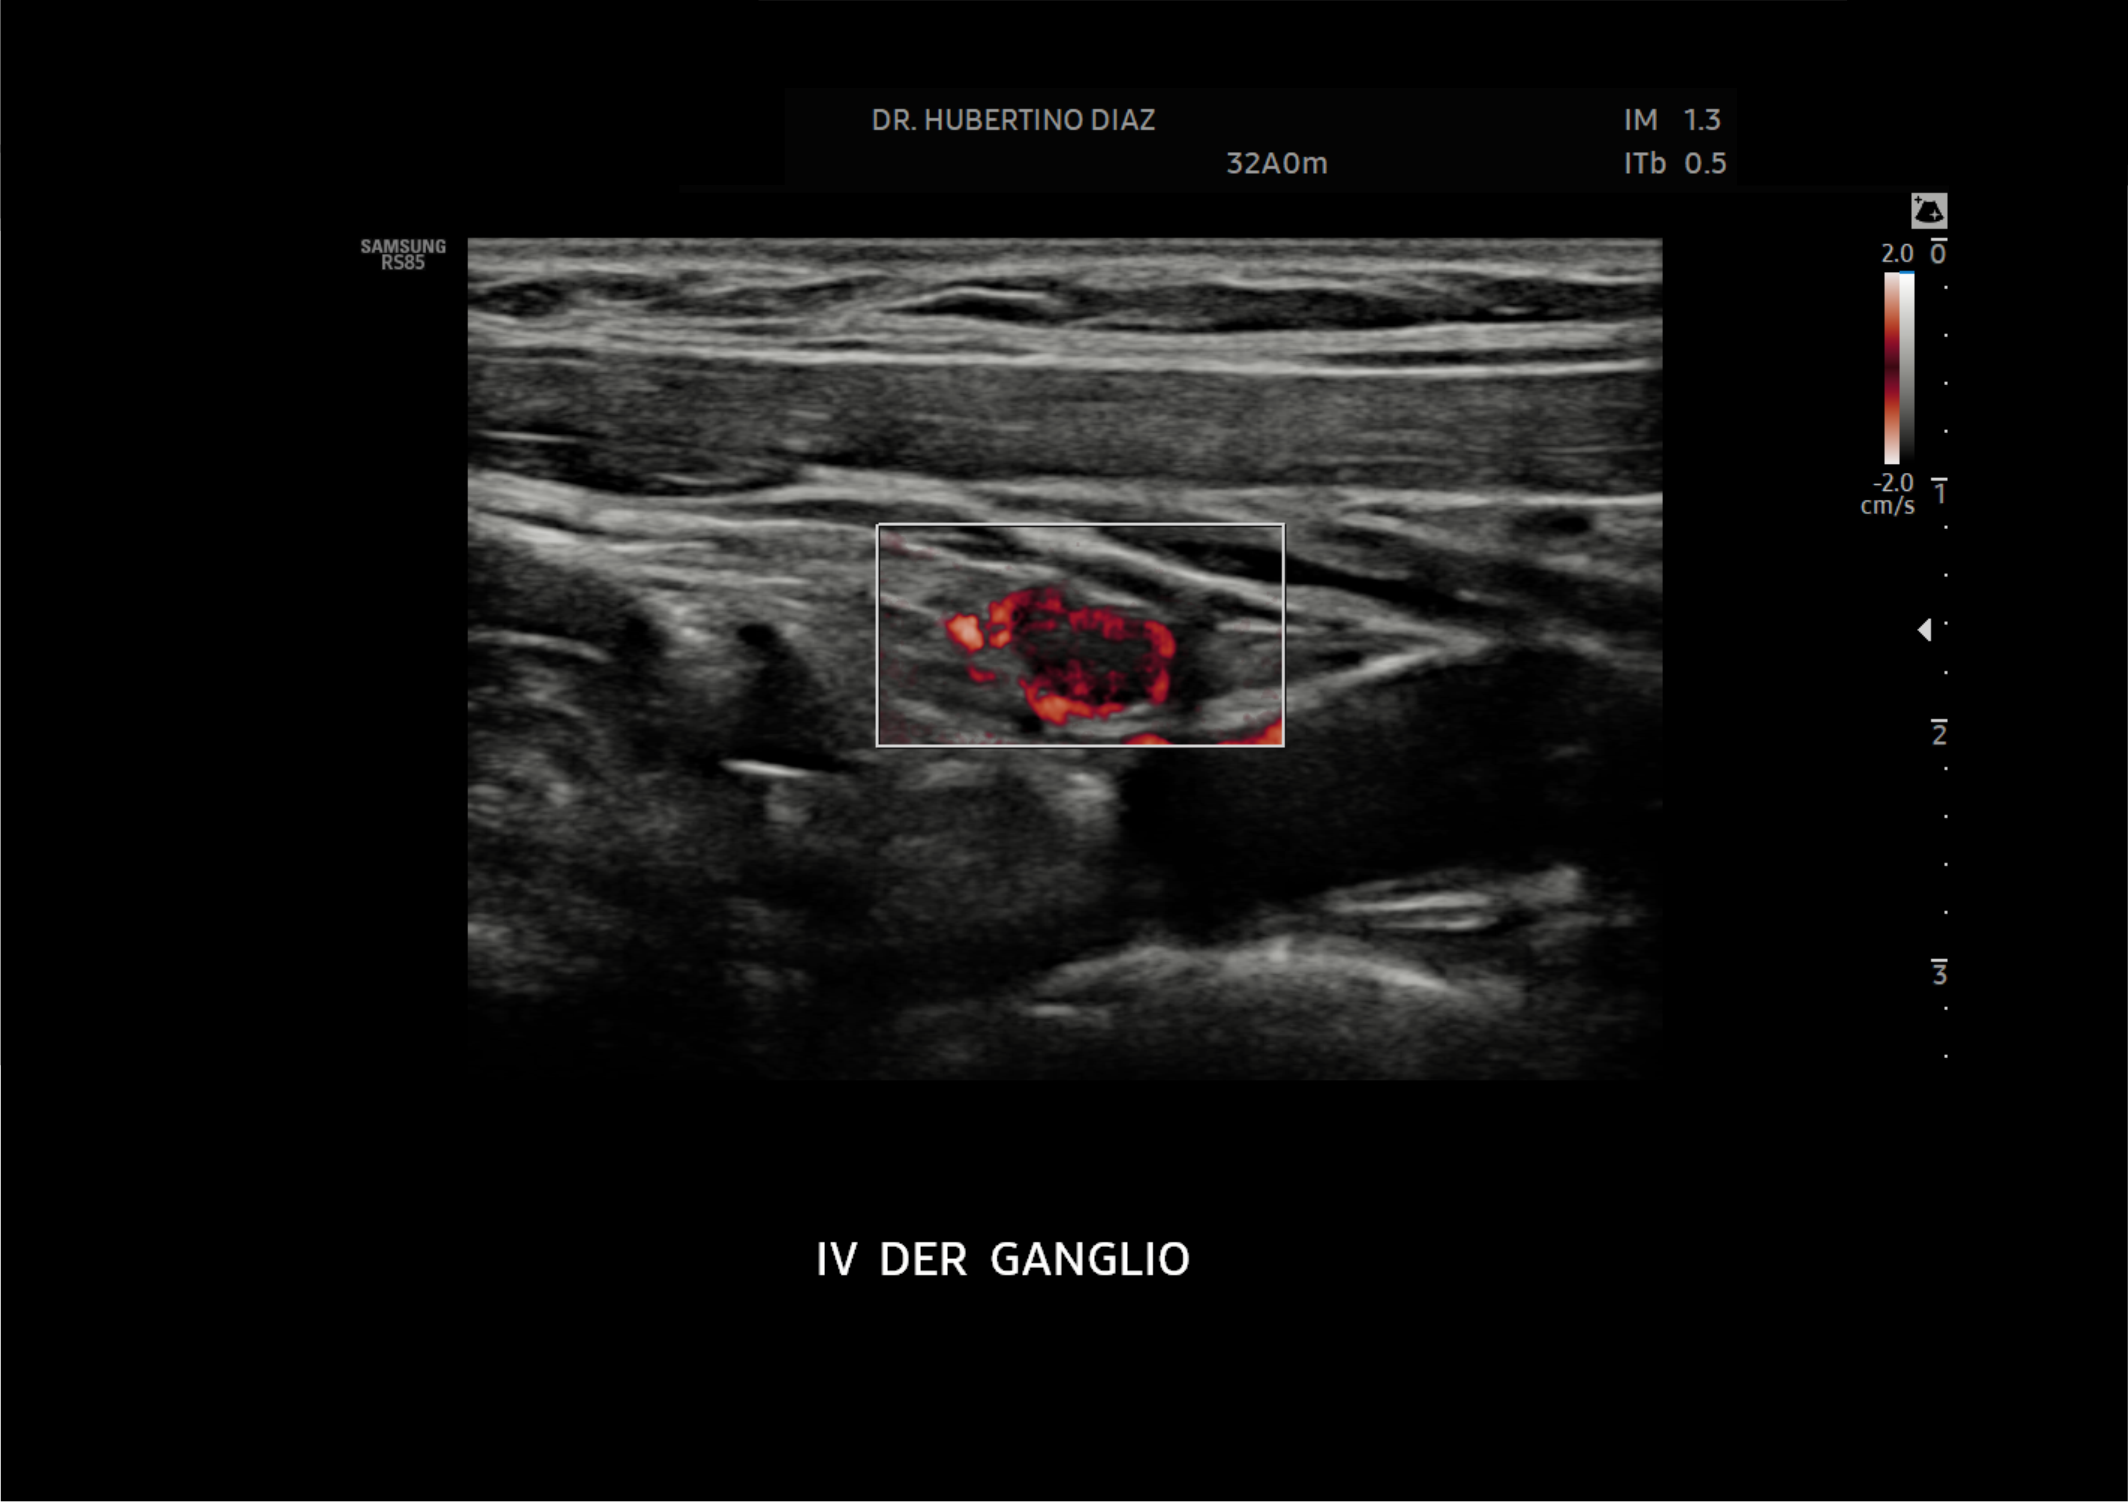

Mediante ultrasonido de alta resolución y tecnología Doppler color, este estudio permite analizar la vascularización de los ganglios linfáticos, lo que aporta información importante para diferenciar entre ganglios inflamatorios, infecciosos o ganglios sospechosos de enfermedad tumoral.

La ecografía Doppler de ganglios en Lima es especialmente útil en pacientes con ganglios aumentados de tamaño, masas palpables o sospecha de enfermedades infecciosas, inflamatorias u oncológicas. Además, permite seleccionar con mayor precisión los ganglios que pueden requerir biopsia guiada por ecografía.